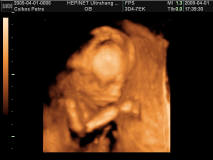

És Petra,Neked is a sztárfotóhoz és az eredményekhez!!